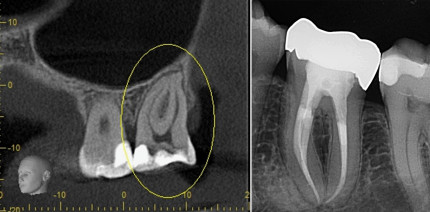

Die Aufbereitung sklerosierter Wurzelkanäle stellt in der Endodontie eine besondere Herausforderung dar. Dieser Fallbericht zeigt, wie durch...

Die Aufbereitung sklerosierter Wurzelkanäle stellt in der Endodontie eine besondere Herausforderung...